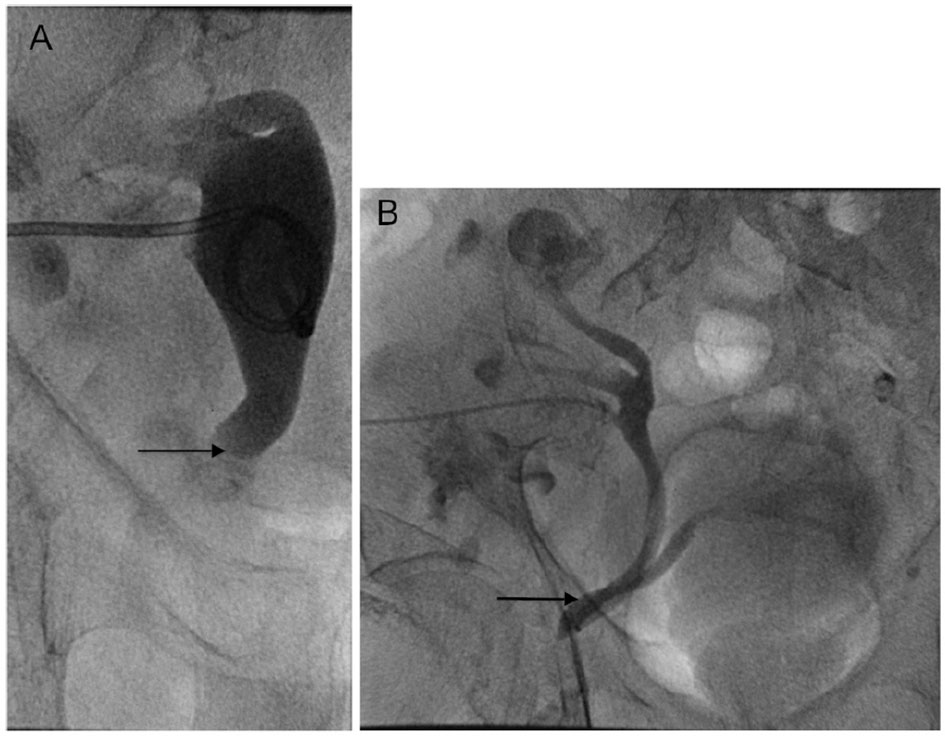

The condition is often diagnosed incidentally during or after herniorrhaphy, when the ureter is inadvertently injured. This highlights the importance of preoperative diagnosis. Anterograde or retrograde urography, computed tomography (CT), or magnetic resonance imaging (MRI) can be used as diagnostic imaging studies. A ureteral hernia can be demonstrated on an anterograde nephrostogram by a redundant loop of ureter, called the “curlique” or “loop the loop” sign (Fig. 1B, arrow). This finding is pathognomonic of a ureteral hernia. The loop is oriented vertically in inguinal hernias, and horizontally in ureterosciatic hernias. CT or MRI with or without intravenous contrast can also make the diagnosis when the distal ureter is seen entering the inguinal canal or extending beyond the bony pelvis [6]. Furthermore, one must have a high index of suspicion for the diagnosis if there is new or unexplained hydronephrosis present ipsilateral to the hernia, or if hydronephrosis is present in the setting of a renal transplant. In these cases, CT urogram, diuretic renogram, or retrograde pyelogram may be indicated prior to surgical intervention.

![]() Click for large image | Figure 1. (A) Nephrostogram immediately before nephrostomy tube placement shows severe hydroureter to the level of the pubic ramus (arrow), proximal to the site of ureteral incarceration. (B) Nephrostogram performed after the nephrostomy tube placement 2 months prior shows the urinary tract to be patent, but barely. The arrow demonstrates the site of ureteral incarceration in the inguinal hernia. Tube nephrostogram showed good internal drainage of the transplant kidney, and extravasation of contrast into the bladder is demonstrated. |